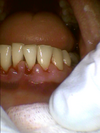

Le cas clinique ci-dessous est issu d'un patient se plaignant de mauvaise haleine, de saignement et de déchaussement dentaire.

Nous lui avons proposé un assainissement parodontal afin de nettoyer en profondeur les dents et gencives.

L'assainissement est un soin simple sous anesthésie qui, le plus souvent accompagné d'un traitement locale, aboutit à une cicatrisation gingivale et une diminution significative du phénomène inflammatoire.

Présence de TARTRE